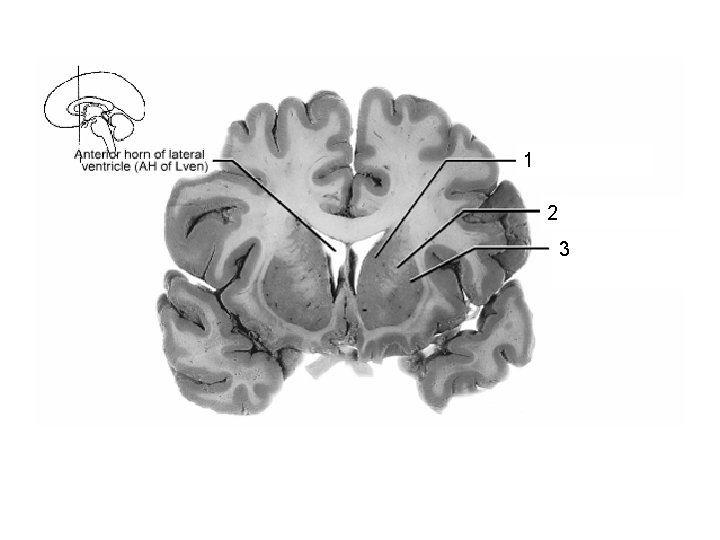

1 2

1 2 3

1 Thalamus 2 3 4

1 Thalamus 2 3 Lentiform Nucleus

1 2 Putamen 3 (lentiform nucleus)

ant. limb, Int. capsule (frontal eye field fibers) 1 head of caudate nucleus 2 frontal horn, lateral ventricle 3 optic chiasm 4 putamen ICA

Post. limb, int. capsule: corticospinal + corticopontine 2 + thalamocortical fibers Body 3 of lateral ventricle thalamus 4 descending cortical 1 fibers in crus cerebri of midbrain 5 Ventricle III Lentiform nucleus 6 putamen is visible) (only